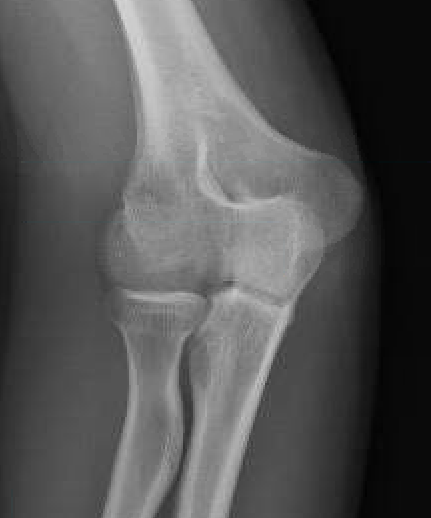

Coronal shear fracture of the distal humerus

Capitellum +/- trochlea

Bryan & Morrey Classification

| Type I | Type II |

|

Large osseous fracture of the capitellum

Articular cartilage injury with little bone |

Hanh Steinthal fracture

Kocher Lorenz fracture |